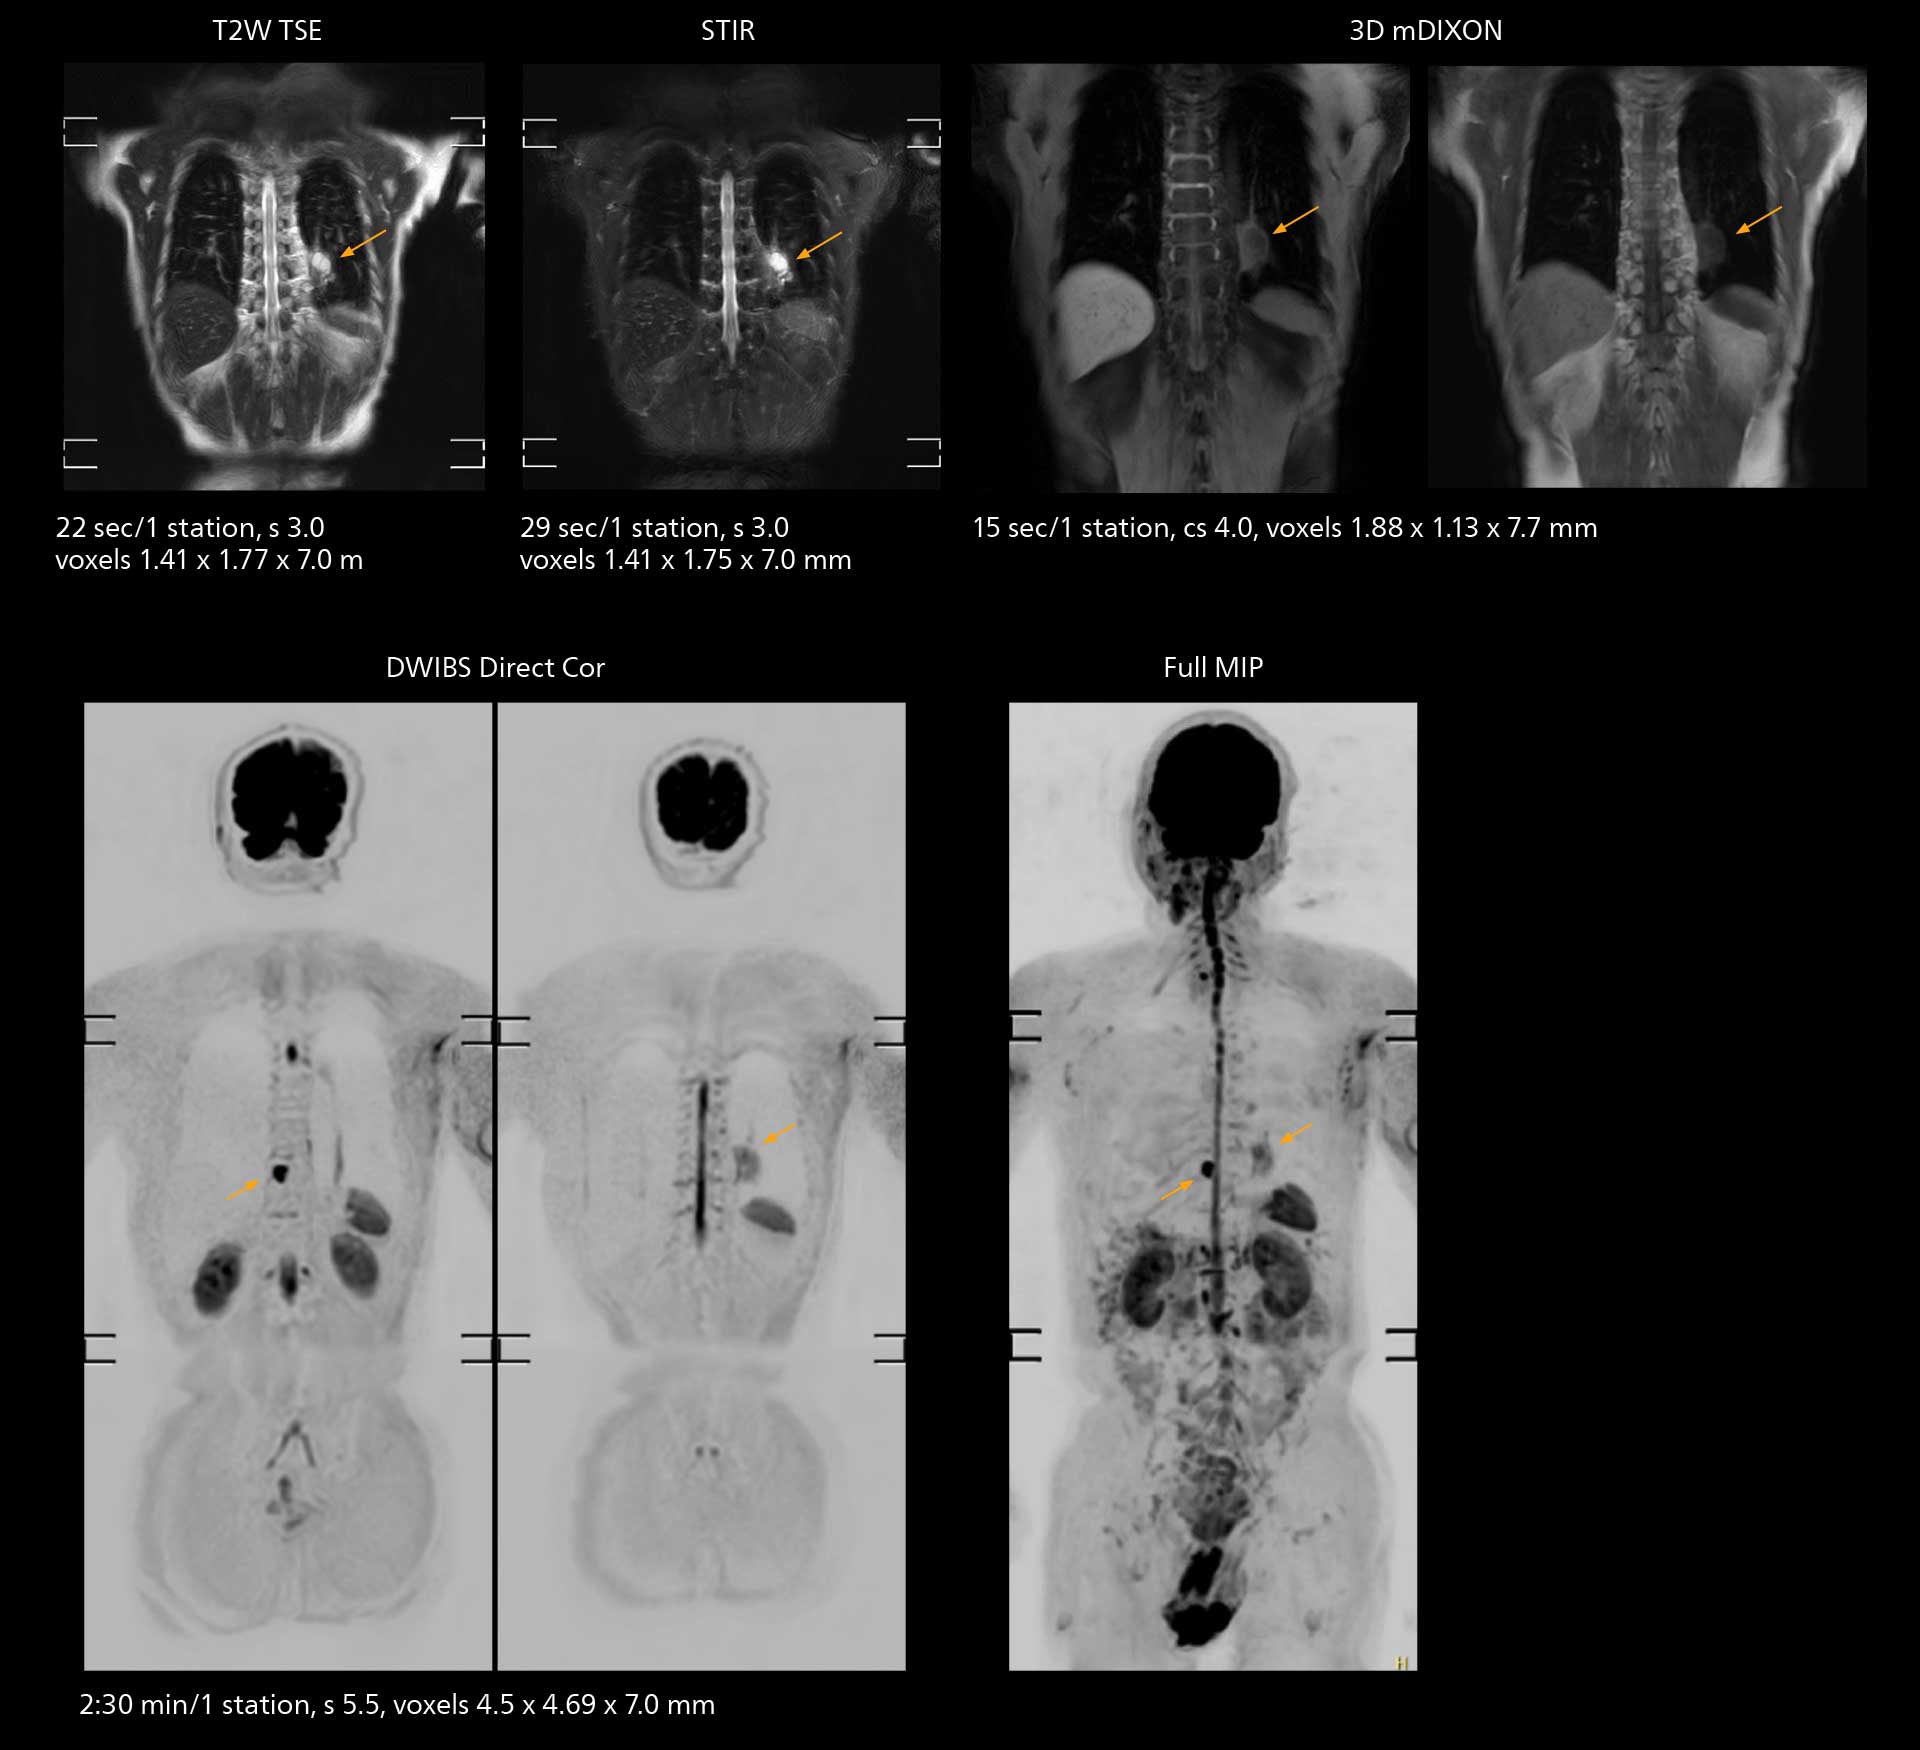

The value of the Elition X gradients is also evident in DWIBS studies. “The fact that we can consistently obtain distortion-free DWIBS while reducing imaging time at three coronal stations is excellent,” Dr. Makuuchi says. “In these patients, it’s also important that the application of Compressed SENSE to T2-weighted, STIR and mDIXON sequences has no impact on the examination time of whole-body imaging. As a result of the increased speed and higher image quality we realize, DWIBS studies have now become routine examinations.”

With SmartPath to Elition X the team can obtain excellent quality DWIBS imaging and reduce imaging time. Other sequences also fit in the examination slot. This case shows left paravertebral neurogenic tumor and Th10 vertebral hemangiomas.